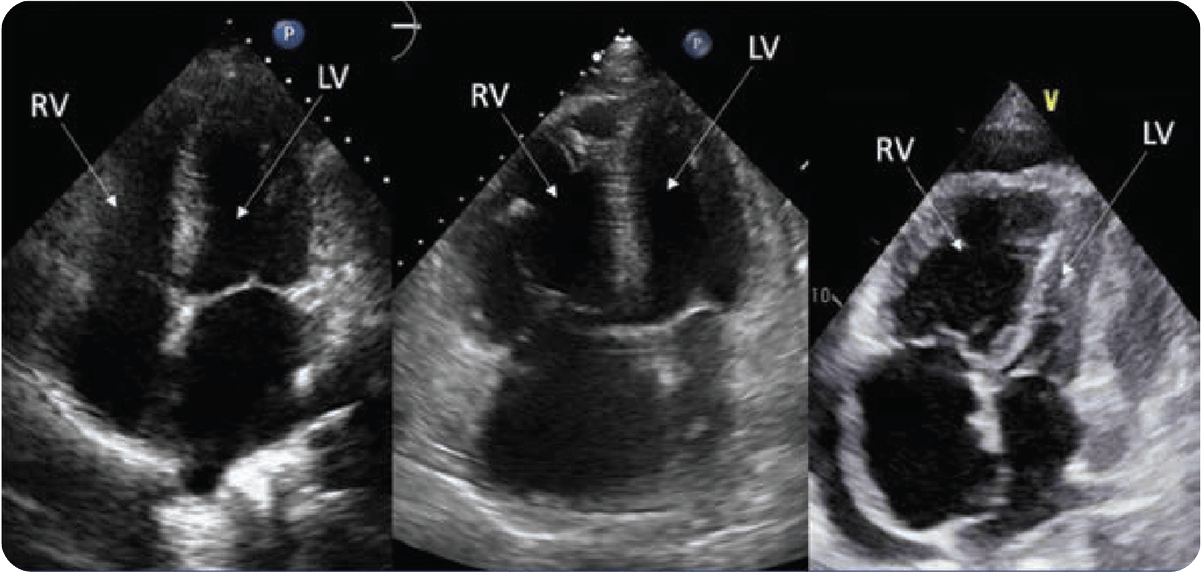

RV Changes Occur Before Other Indicators of PAH Progression2

- Both REVEAL Lite 2 and the updated 2022 ESC/ERS Guidelines emphasize using echocardiography when assessing RV function and its effect on PAH progression1,5

- A TAPSE of ≤18 mm or moderate/severe tricuspid regurgitation (TR) have been associated with worse outcomes in the intermediate risk PAH population6